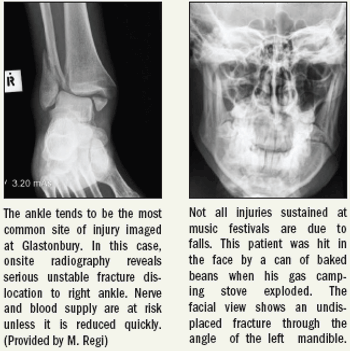

Music, alcohol, perhaps a few drugs, little sleep, and an extremely slippery dance floor make for an undeniably dangerous cocktail.

A combination of loud music, alcohol, drugs, and rainy weather churn a dangerous brew that can lead to musculoskeletal injuries. At the U.K.’s mammoth Glastonbury music festival in June they were evaluated with onsite diagnostic imaging services.